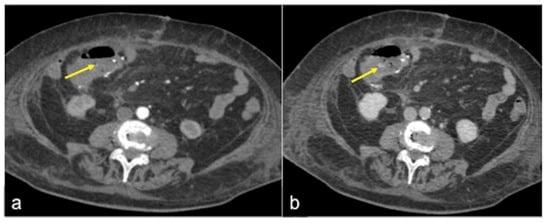

| Diverticulosis (Figure 33) | Asymptomatic or bleeding. | Protruding sacs where the vessels pass through the muscularis layer, between the mesenteric and antimesenteric taenia. |

| Angiodysplasia (Figure 5 and Figure 34) | Asymptomatic or bleeding. | Small hyperdense nodules within the intestinal wall, best defined in the portal phase of the study. |